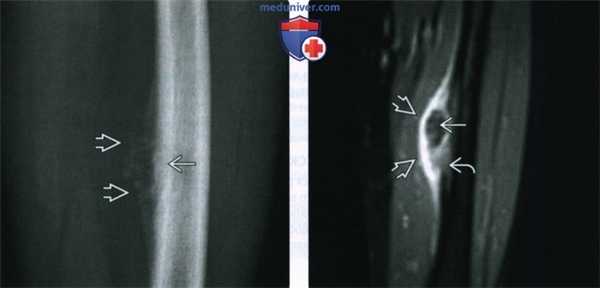

(Слева) Показан срез через остеосаркому (ОС). Новообразование разрушает костную архитектуру и прорывается через кортикальный спой с образованием периферического мягкотканного компонента. Показана аморфная остеоидная ткань, как в кости, так и в мягких тканях.

(Справа) Рентгенография в ПЗ проекции, женщина 25 лет: визуализируется плотная склерозированная остеоидная опухоль, замещающая метадиафизарный костный мозг и мягкотканное образование, которое содержит как плотный, так и аморфный опухолевый остеоид. Обычная остеосаркома здесь является единственным возможным диагнозом. (Слева) МРТ, корональная проекция, режим T1: у этой же пациентки визуализируется гипоинтенсивное образование, замещающее костный мозг. Зона сигнала наименьшей интенсивности соответствует опухолевому остеоиду. Визуализируется мягкотканный компонент, который смещает мягкие ткани.

(Справа) МРТ, корональная проекция, режим Т1 с подавлением сигнала от жира, с контрастным усилением: вдоль гипоинтенсивного опухолевого остеоида визуализируется ткань, накапливающая контрастное вещество. Визуализируется гиперинтенсивная периостальная реакция и опухоль, распространяющаяся через кортикальный слой. Это чрезвычайно злокачественное новообразование.